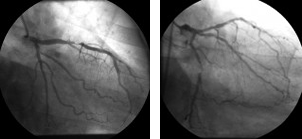

Ai fini della valutazione dell’entita’ della patologia coronarica, si parla di stenosi significativa quando si ha una stenosi coronarica superiore o uguale al 70%, se i vasi coronarici sono la discendente anteriore, la circonflessa, e la coronaria destra, se si tratta del tronco comune allora la stenosi deve essere superiore al 50%.

Stenosi ramo discendente anteriore e stenosi ramo circonflesso